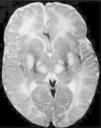

Los ganglios basales (globo pálido, putamen, núcleo caudado, núcleo subtalámico y sustancia negra) son acumulaciones de cuerpos neuronales que tienen como función primordial el control del inicio, amplitud y rapidez de los movimientos4, en un niño con síndrome Leigh la falla en el metabolismo oxidativo y la necrosis de estas estructuras se traduce en defectos del movimiento, por tanto se caracterizan por déficit motor o activación anormal del sistema motor, lo que da lugar a rigidez, temblor y movimientos involuntarios (fig. 3).

Diagnóstico y tratamientoLas manifestaciones clínicas del síndrome se presentan antes de los 6 meses de edad, el médico que evalúa el caso requiere de una gran destreza para poder diferenciar este trastorno de otros trastornos mitocondriales que presentan características similares y con los cuales se puede confundir, para un diagnóstico diferencial adecuado se debe hacer uso de recursos como; biopsia muscular para analizar el funcionamiento de la cadena respiratoria y poder identificar el error en los complejos enzimáticos, así mismo el uso de resonancia magnética y tomografía computarizada que permite identificar la necrosis de los ganglios basales, característica principal del síndrome de Leigh.